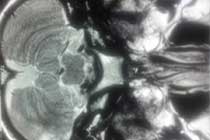

Brain Abscess Brain Abscess Post OP 2 Clinical Intra OP ,After Excising The Granuloma Intaop Scalp Abscess CT Scalp Abscess Cerebellar Abscess Post OP Clinical Cerebellar Abscess Brain TB Granuloma Post OP CT Scan Brain Infection Brain Abscess Preop MRI 2 Brain Abscess PRE OP Clinical 1 Brain Abscess PRE OP Brain Abscess Intraop 2 Brain Abscess Following Shunt Temporal Abscess T2W of TB Granuloma Scalp Abscess Preop CT Marking PRW OP MRI of TB Granuloma Post OP Clinical Photo Post OP Cerebellar Abscess Post OP Brain Abscess Intraop Specimen of Granuloma